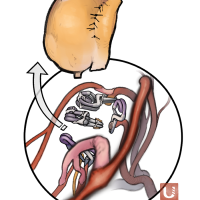

FEN2022シリーズ